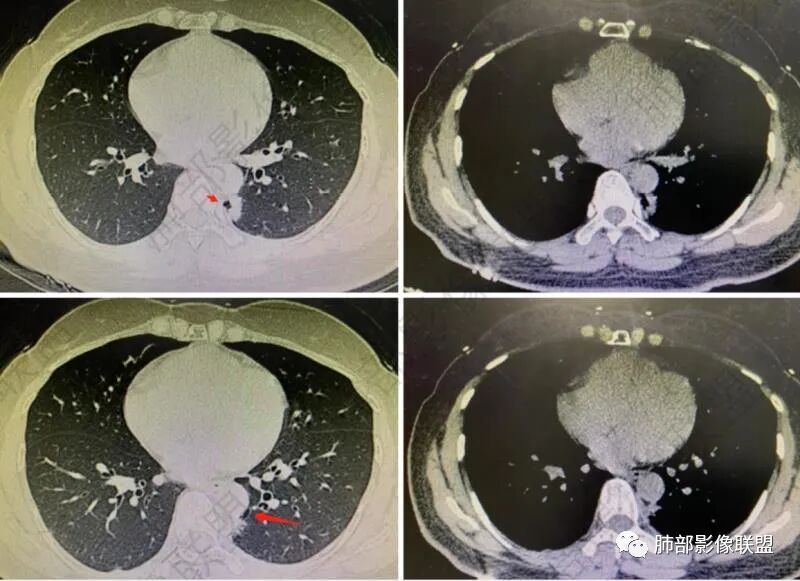

女性,体检发现,右肺上叶后段麿玻璃影!考虑AAH,左肺下叶病灶,外有毛刺伴囊腔样改变,考虑腺癌可能性大。

左肺下叶胸膜下不规则结节,边界清,短毛刺及囊腔,支气管扩张,邻近胸膜增厚,右肺上叶磨玻璃结节,边界清,考虑左肺下叶腺癌,右肺上叶AIS,鉴别炎性结节。

左肺下叶胸膜下结节,呈不规则型,边缘分叶、毛糙,内囊腔可见分隔,考虑腺癌,鉴别隔离症,右肺上叶磨玻璃结节,建议随诊。

右肺结节AIS,左肺下叶,边界似清不清,假大空,粘液腺癌要考虑。

年轻女性,左肺下叶考虑肺腺癌,右肺上叶结节,倾向AIS。一元论不排除隐球菌/其它肉芽肿性病变可能。

右肺上叶微结节边缘光滑,左肺下叶磨玻璃结节影,边界不清,左肺下叶脊柱旁斑片影,边缘未见明显磨玻璃密度影,内多个空腔影,较大者似见与支气管相通,首先考虑慢性炎症性改变,右肺上叶AIS,左肺下叶磨玻璃,炎性改变待排,抗炎后复查。

中年女性,体检发现,右肺上叶后段纯磨玻璃类圆形病灶,边缘清,左肺下叶背段纵隔旁示不规则高密度影,可见空泡影,边缘欠清。1、右肺上叶病灶考虑AAH-AIS 2、左肺下叶病灶考虑腺癌。

左肺下叶胸膜下不规则结节,边界清,短毛刺及囊腔,假大空 支气管扩张,邻近胸膜增厚,右肺上叶磨玻璃结节,边界清,考虑左肺下叶腺癌,右肺上叶AIS,鉴别炎性结节、隐球菌。

左肺下叶后基底段结节,边缘凸起,不规则,血管进入,假太空及小叶间隔特点(恶性征象之一),另结节壁层胸膜下脂肪间隙消失,两肺多发散在磨玻璃结节,右肺上叶后段圆圈征,双肺下叶胸膜下分布,纵隔内淋巴结肿大,考虑粘液腺Ca并两肺气道种植转移,与PC鉴别,建议隐球荚膜抗原检查。

右肺上叶磨玻璃结节,边缘清晰,考虑AAH。左肺下叶脊柱旁结节,周围见多发空泡,边缘模糊,胸膜粘连,考虑肉芽肿可能。